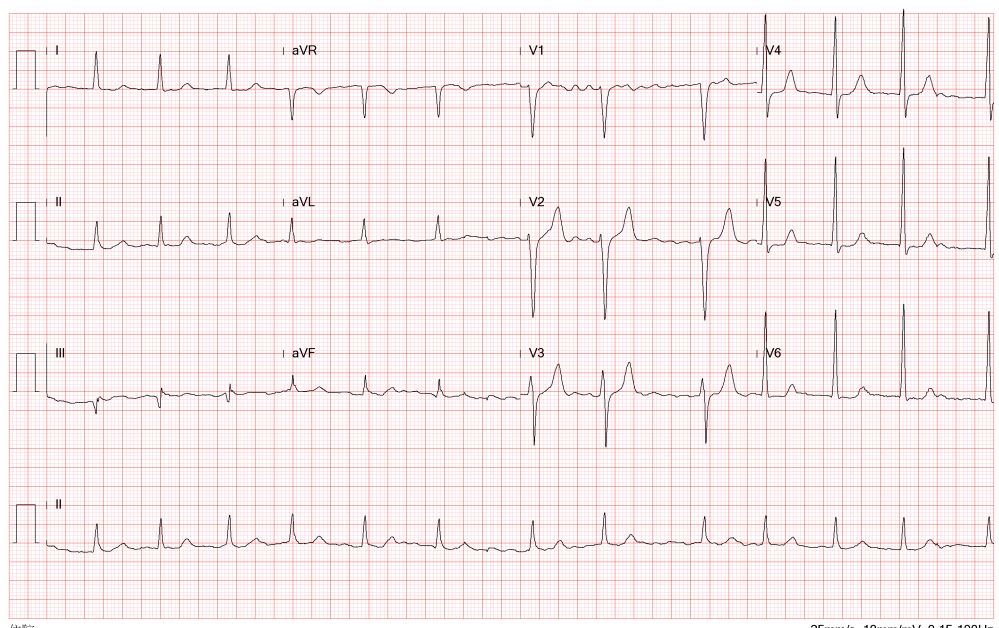

Transesophageal echocardiography revealed severe aortic regurgitation due to THV leaflet perforation following untreated infective endocarditis, along with a preexisting paravalvular leak caused by the calcified raphe of the type 1 bicuspid aortic valve.Given the patient’s deteriorating clinical status despite inotropic support, and after three negative blood cultures and five weeks of antibiotic treatment, the heart team decided to proceed with transcatheter treatment.